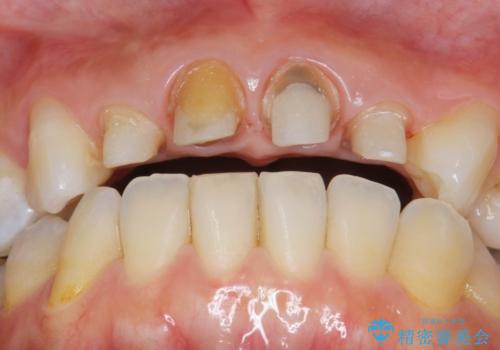

- 「黒ずんで、見栄えの悪い前歯をきれいにしたい。」と、前歯のセラミック治療を希望され来院されました。

全て根管治療のすでになされている歯の変色で、オールセラミッククラウンによる審美性の改善を計画します。

- 52.8万円(ジルコニアクラウン×4・仮歯×4)費用は治療当時の料金となります